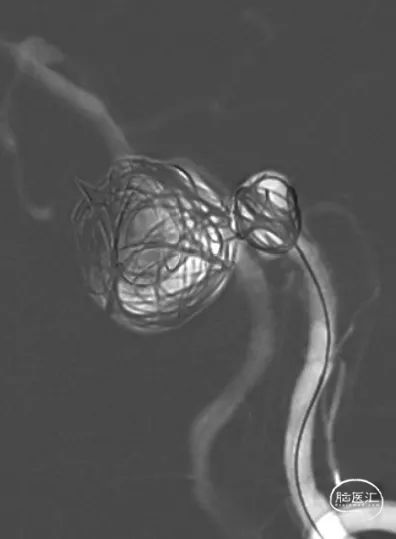

FRED支架释放后,支架CT提示支架贴壁良好

使用25×50、25×50 axium弹簧圈栓塞基底动脉瘤后,使用14×40、10×30、8×30、5×20、3×8 5枚弹簧圈栓塞椎动脉瘤及闭塞左椎动脉末端

经左椎动脉造影,弹簧圈最终完全闭塞左椎动脉V4段,附近的脊髓后动脉保留

经右椎动脉最终造影

2、血流导向装置可以在尽可能保护穿支的前提下,治疗动脉瘤。而少量弹簧圈填充可以促进动脉瘤愈合。

3、患者双侧椎动脉均势发育,一期栓塞左椎动脉瘤及左椎动脉,不会导致严重后循环缺血症状,同时有助于血流导向装置的导流作用,促进基底动脉瘤的愈合。但栓塞椎动脉时,要关注附近的重要血管分支,比如脊髓后动脉。

3、基底动脉瘤内少量弹簧圈填塞,保护动脉瘤相对薄弱区域,纠正载瘤动脉的喷射血流,减少围手术期动脉瘤破裂风险,促进动脉瘤愈合。